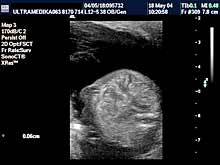

A) I trimestar do 14

nedelje gestacije

(3 meseca + 2 nedelje)

Indikacije za ultrazvučni pregled:

- Izostanak menstruacije, procena vitalnosti rane trudnoće,

procena materične i/ili postojanje vanmaterične trudnoće.

(Od 4-7 nedelje gestacije, ili prva 2 meseca od prvog dana zadnje

menstruacije).

- GENETSKI SONOGRAM (2 - 3 ½ meseca):

- Otkrivanje ultrazvučnih markera na postojanje hromozomskih

anomalija ploda (SKRINING na ANEUPLOIDIJE). Ovaj genetski sonogram

treba uraditi dva puta u intervalu od 9 do 14 nedelje gestacije uz

biohemijsku proveru iz krvi trudnice nakon tačne ultrazvučne procene

veličine ploda. Genetski sonogram sam isključuje oko 88% trizomija,

a udružen sa biohemiskim analizama se isključuje oko 98%

aneuploidija.

- Prva procena i otkrivanje krupnih anatomskih anomalija ploda

koje ne moraju pratiti hromozomske anomalije.

- Prva procena posteljične cirkuacije Broandband - CD

- Pregled materice i organa male karlice kao i organa abdomena

trudnice.

Način pregleda:

- transabdominalno i/ili endovaginalno

(bez prethodnog punjenja

mokraćne bešike).

Primenjena tehnika:

- Broadband 2D,

- harmonik mod,

- Sono CT,

- XRes,

- 3D Sono CT,

- CPA.

NAPOMENA:

Ultrazvučni markeri za aneuploidije nestaju nakon I

trimestra trudnoće. Nakon toga ove markere nije moguće registrovati.

Blagovremeno otkrivanje dovodi do prekida trudnoće u dozvoljivom

vremenskom terminu. Brojne anatomske anomalije su dostupne otkrivanju

u ovom periodu trudnoće.

Ako su ultrazvučni markeri nedostupni pregledu, genetski sonogram

podrazumeva upotrebu trodimenzionalne tehnike - 3D Sono CT i CPA. |